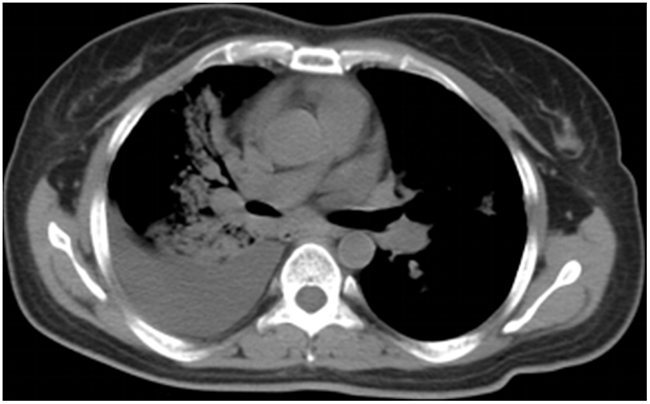

Clinical examination revealed pulmonary alveolar respiratory sounds were weakened in right lower lung. Pulmonary mass in right central lung, multiple irregular nodules scattered in bilateral lung and right pleural effusion were observed on chest X-ray. Contrast CT scan showed enlarged bilateral mediastinal lymph nodes, metastases of liver segment 4 and eighth thoracic vertebrae, third and forth lumbar vertebrae (Figure 1). Subsequently, the patient underwent CT-guided percutaneous lung biopsy of the right lung mass. After the procedure, the CT scan showed right side hydropneumothorax, but the chest tube drainage did not needed. Pathologic evaluation confirmed the diagnosis of infiltrating lung adenocarcinoma. EGFR mutation status evaluated by allele specific PCR assays (SNaPshot) and PCR-based direct sequencing both showed exon 21 L858R mutation.

Figure 1: Axial CT image demonstrating pulmonary mass in right central lung, multiple irregular nodules scattered in bilateral lung and right pleural effusion at the time of diagnosis.